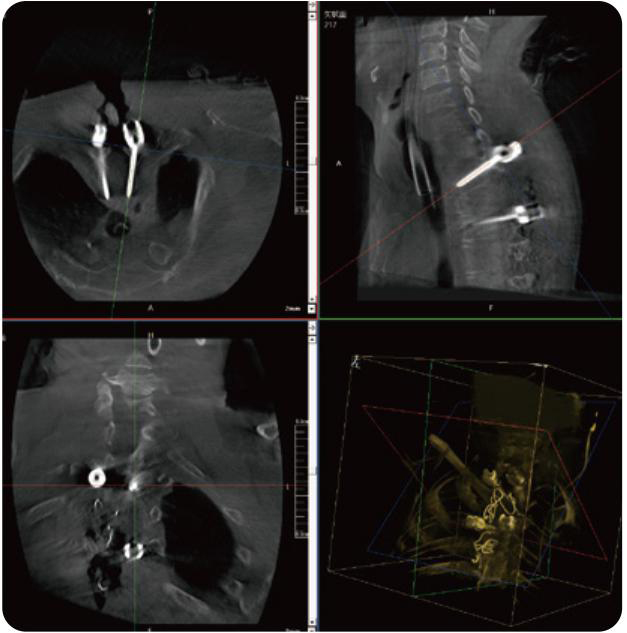

PL300B可應用于多節(jié)段脊柱外科手術,輔助醫(yī)生定位病灶部位,為脊柱外科手術(經(jīng)皮椎體成形術、椎弓根螺釘內(nèi)固定術等術式)提供術前手術流程規(guī)劃、入釘位置、角度可視化引導,模擬仿真入釘輔助。

PL300B搭配普愛醫(yī)療自主研發(fā)生產(chǎn)的平板3D C形臂,借助一體化自適應配準( 軌跡配準)技術,通過追蹤C形臂三維采集軌跡,自動完成圖像坐標建立和系統(tǒng)坐標配準。配準精度更高,操作步驟少,系統(tǒng)運作效率高。